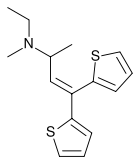

The pharmacodynamic response to an opioid depends upon the receptor to which it binds, its affinity for that receptor, and whether the opioid is an agonist or an antagonist. For example, the supraspinal analgesic properties of the opioid agonist morphine are mediated by activation of the μ1 receptor; respiratory depression and physical dependence by the μ2 receptor; and sedation and spinal analgesia by the κ receptor. Each group of opioid receptors elicits a distinct set of neurological responses, with the receptor subtypes (such as μ1 and μ2 for example) providing even more [measurably] specific responses. Unique to each opioid is its distinct binding affinity to the various classes of opioid receptors (e.g. the μ, κ, and δ opioid receptors are activated at different magnitudes according to the specific receptor binding affinities of the opioid). For example, the opiate alkaloid morphine exhibits high-affinity binding to the μ-opioid receptor, while ketazocine exhibits high affinity to ĸ receptors. It is this combinatorial mechanism that allows for such a wide class of opioids and molecular designs to exist, each with its own unique effect profile. Their individual molecular structure is also responsible for their different duration of action, whereby metabolic breakdown (such as N-dealkylation) is responsible for opioid metabolism.

There are a number of broad classes of opioids:[260]

- Fully synthetic opioids: such as fentanyl, pethidine, levorphanol, methadone, tramadol, tapentadol, and dextropropoxyphene;